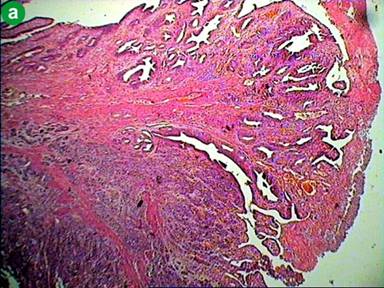

Patient underwent surgery, where a large mass of size 3 cm was found in the periampullary region with absence of body and tail of the pancreas confirming the diagnosis of agenesis of dorsal pancreas. A total pancreatectomy, duodenectomy, Roux-en-Y gastrojejunostomy, hepaticojejunostomy, and cholecystectomy were performed. On gross examination, a large ulceroinfiltrative lesion (3.0×2.5×2.0 cm) involving mostly periampullary region was found which was firm in consistency, pale greyish white in appearance with ill defined edges appearing to invade almost full thickness of the duodenal wall extending onto subserosa (Figure 3). Histopathological examination revealed invasive poorly differentiated adenocarcinoma with diffuse deep infiltration involving almost full thickness of the duodenal wall and invading subserosa (Figure 4a). Immunohistochemistry was done and the tumor cells were positive for immunohistochemical markers CA 19-9 (Figure 4b), cytokeratin-7, KI-67 (Figure 4c) and negative for CEA, cytokeratin-20. No lymph node metastasis was found.

Figure 4. a. Histopathological image of periampullary lesion (low power view) showing diffuse infiltration of tumor cells up to serosa off duodenum. b. Immunohistochemical staining of poorly differentiated tumor showing positive for tumor marker CA-19-9 and KI-67. c. Immunohistochemical staining of poorly differentiated tumor showing positivity for proliferative marker Ki-67. |

Our patient had periampullary carcinoma with agenesis of dorsal pancreas. Periampullary carcinoma is a tumor arising in the vicinity of the ampulla of Vater [17]. They can originate from the pancreas, duodenum and distal common bile duct [18]. These tumors are classified on the basis of their tissue of origin; they are different from the classical adenocarcinoma of the pancreas and they may be either benign or malignant tumors. Pathological examination of these tumors showed that 60% of are of pancreatic origin, 20% from ampulla of Vater, 20% from common bile duct and rest 10% arise from duodenum [18]. In literature around 9 cases pancreatic cancer have been reported in association with agenesis of dorsal pancreas. Among these pancreatic ductal adenocarcinoma was the most frequent, being reported in 5 patients, solid papillary tumor in 2 patients, IPMN with well differentiated, invasive mucinous adenocarcinoma in 1 patient and 1 patient with periampullary carcinoma [11, 19-23]. Only one case of periampullary carcinoma was reported by A Kapoor et al. [23] from India and ours is the second case. Our case had poorly differentiated adenocarcinoma and we did immunohistochemistry. Immunohistochemistry showed, tumor cells were positive for markers CA 19-9, KI-67, cytokeratin-7 (Figure 4b and 4c) and negative for intestinal markers like cytokeratin-20 and CEA (carcinoembryonic antigen) suggestive of pancreatico-biliary type of poorly differentiated adenocarcinoma. Pancreatico-biliary tumors follow a more aggressive course similar to that of pancreatic adenocarcinoma with worse prognosis. Our patient underwent total pancreatectomy and post operatively she developed insulin dependent diabetes mellitus.